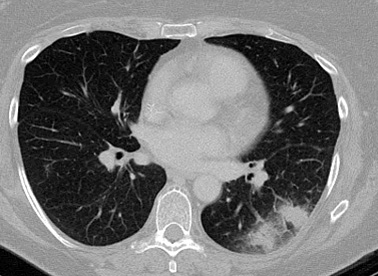

Sinal de "halo" em aspergilose pulmonar inicial

Do acervo do Dr. P. Chandrasekar; usado com permissão

Veja esta imagem em contexto nas seguintes seções: